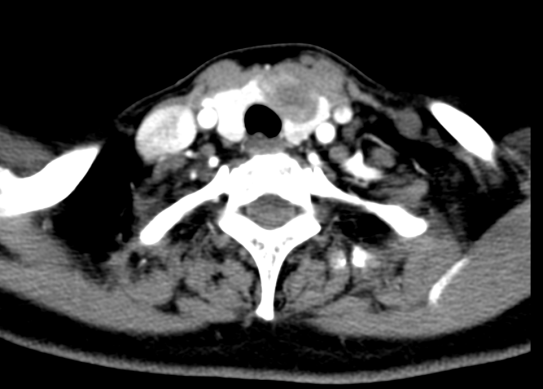

(一)气管压迫与粘连危机:肿瘤体积巨大且紧贴气管生长,影像显示气管明显受压变形,术中稍有不慎即可能引发大出血或气道塌陷;

嗓音评估显示声带活动对称,发音清晰度完全恢复至术前水平;血钙监测证实甲状旁腺激素(PTH)及血钙值均正常,彻底规避了低钙抽搐风险。复查CT确认肿瘤完整切除,气管压迫完全解除,患者术后第3天即可下床活动,康复进展顺利。